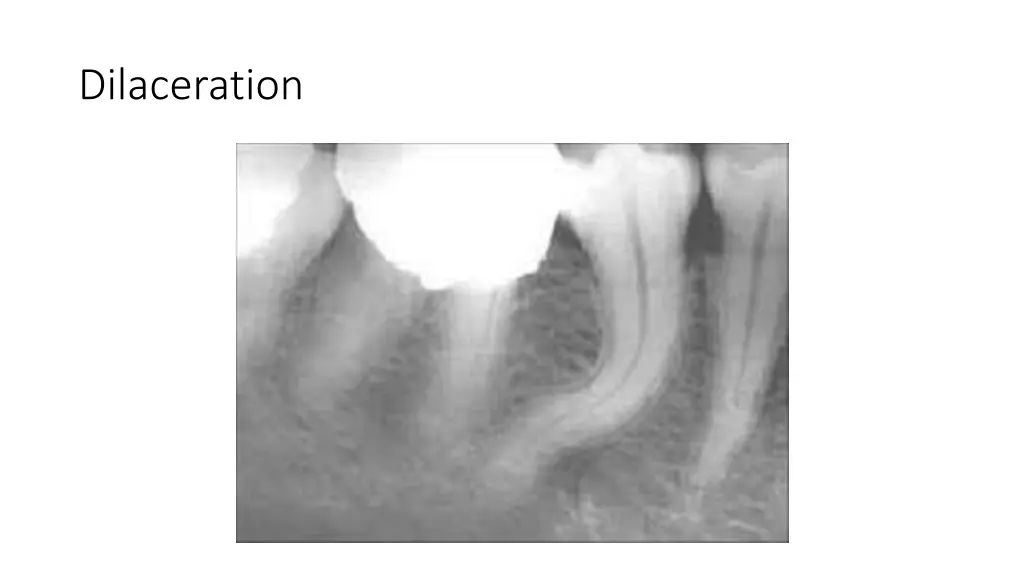

True Anodontia, Partial True Anodontia, Partial False Anodontia, Mesiodens/Supernumerary, Microdontia, Marcrodontia, Gemination/Right Fusion/Left, Peg-Lateral, Fusion Two Roots/Two Crowns, Dens in dente, Dilaceration, Concresences, Taurodontia, Hypercementosis, Amelogenesis Imperfecta, Dentinogenesis Imperfecta, Hutchinson Incisors, Mulberry Molars, Mental Foramens - Radiolucent.